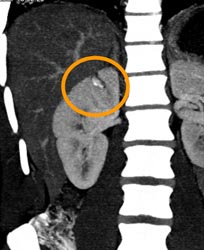

Renal Laceration